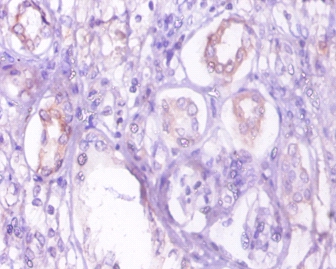

Immunohistochemical analysis of paraffin-embedded human kidney using #42288 at dilution of 1:10.

Catalyzes the conversion of oxaloacetate (OAA) to phosphoenolpyruvate (PEP), the rate-limiting step in the metabolic pathway that produces glucose from lactate and other precursors derived from the citric acid cycle.